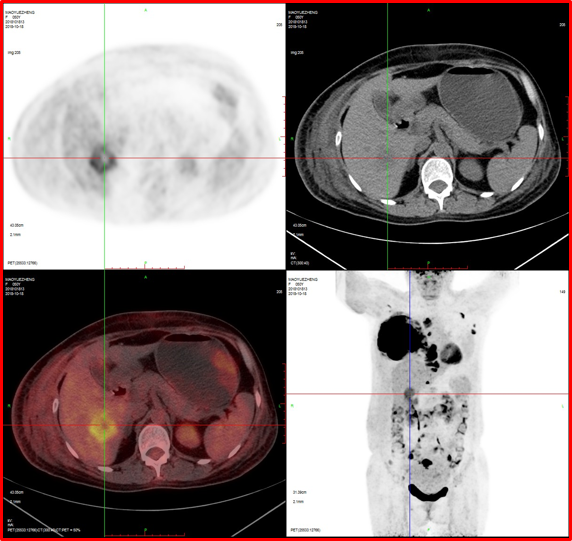

病例3:男性,72歲。結(jié)腸腺癌術后3年,右肺鱗癌術后1年隨訪。

4、肝脾多發(fā)轉(zhuǎn)移灶可能。